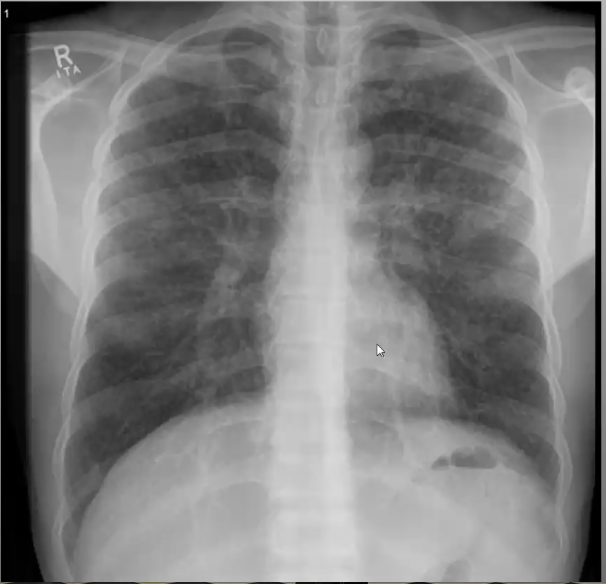

What’s your diagnosis?

Right middle lobe pneumonia because loss of right heart border (silouhette sign)